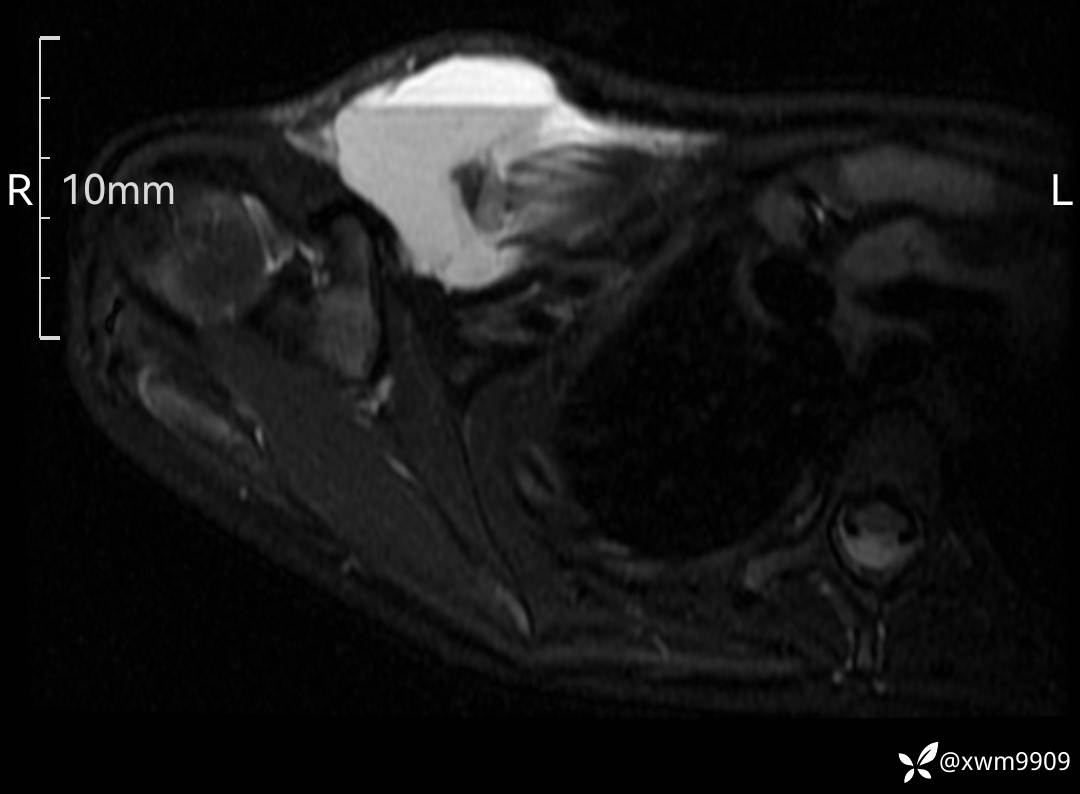

3、查体,右锁下方可及一约5x6Cm肿物,软丶边清丶未见明显发红,肤温不高,压痛明显,不可推动,稍有波动感。其他无特殊。

2、CT、MR肿块内可见液-液平面,常见有哪些疾病。